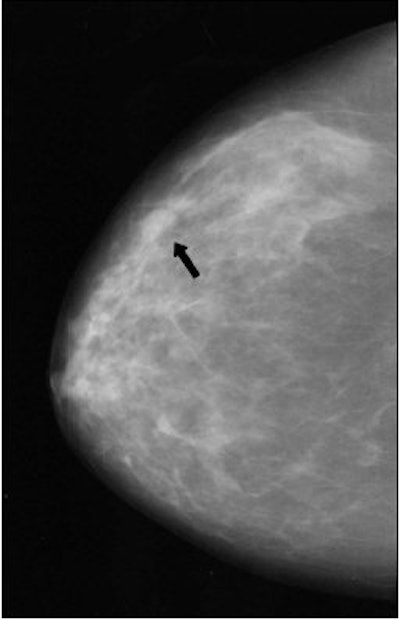

| Fifty-eight-year-old woman who presented with "pulling" on the inner left breast, diagnosed with bilateral invasive ductal carcinoma after biopsy. Above is the craniocaudal view mammogram. Cancer in left breast at point of clinical finding is apparent. A second cancer (arrow) was detected in the right breast. Butler SA, Gabbay RJ, Kass DA, Siedler DE, O'Shaughnessy KF, Castellino RA, "Computer-Aided Detection in Diagnostic Mammography: Detection of Clinically Unsuspected Cancers," (AJR 2004; 183: 1511-1515). |

A total of 761 images were reviewed. The most common clinical finding that prompted a diagnostic mammogram was a palpable mass (90%). A single biopsy-proven cancer was identified in 92.4% of the women with an additional cancer at a second site found in 7.6%. These clinically unsuspected cancers found at an unrelated site -- 30 in total -- appeared on mammography as either mass, architectural distortion, or microcalcification clusters. The 30 cancers allowed a measurement of the potential benefit of CAD, the authors wrote.